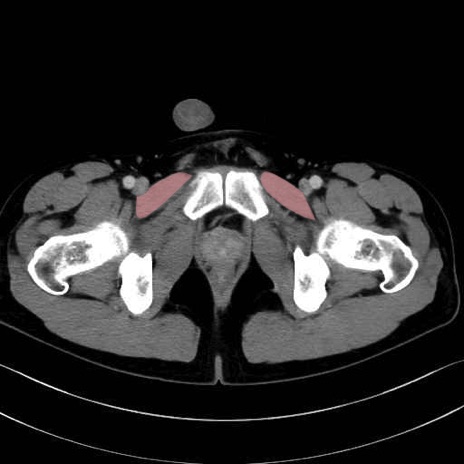

恥骨筋 (Pectineus)

長内転筋 (Adductor longus)

短内転筋 (Adductor brevis)

大内転筋・小内転筋 (Adductor magnus / Adductor minimus)